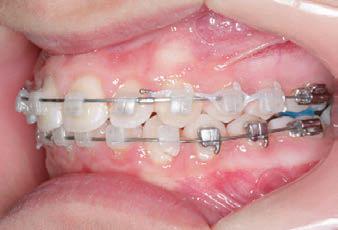

CLASS II DIV.1 - Marra

INITIAL - 4/4/18

PROGRESS 1 - 26/9/18 - Class I platform accomplished in 5.75 months with Motion 3D COLOR Appliance

PROGRESS 2 - 26/9/18 - Placement of the SLX 3D Clear Brackets

with M-ONE .015 Cu Nitanium 27°

PROVIDED BY: DR. LUIS

PROGRESS 3 - 30/10/18 - With M-TWO .020 x .020 Cu Nitanium 35° archwire

PROGRESS 4 - 27/11/18 - 3 links power chain: 5, 4, bypass 3 to crimp hooks

PROGRESS 5 - 13/3/19 - With M-TWO .020 x .020 Cu Nitanium 35° archwire

PROGRESS 6 - 1/8/19 - With M-THREE.019 x .025 Beta Titanium wire